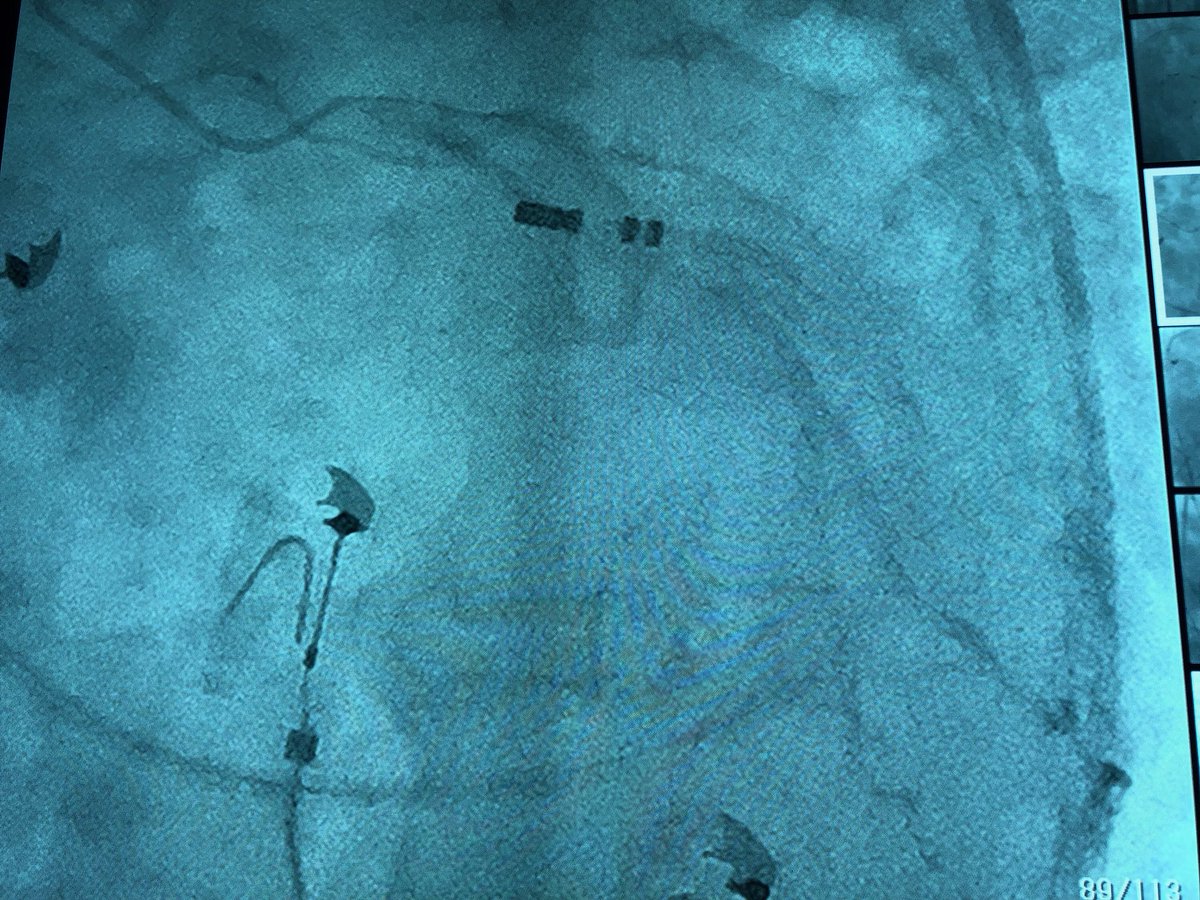

High MDI had me concerned about Epi or intramural origin. Early in AIV on top of LCX, matched opposite location in LCC and was 20-25ms earlier, success with 35w. #ablatePVC